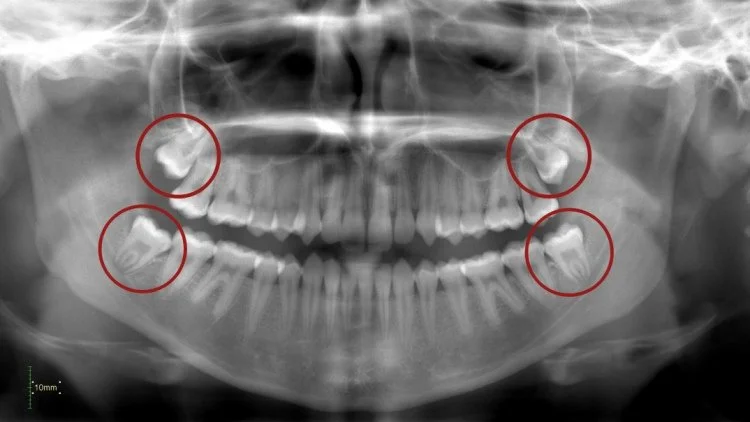

Röntgenfoto voor verstandskiezen voor tandextractie verwijdering van tand of kies

• Verstandskiezen, ook wel derde molaren genoemd, zijn de laatste kiezen die doorkomen in de mond, meestal tussen de leeftijd van 17 en 25 jaar. Hoewel ze nuttig kunnen zijn als ze goed doorkomen, veroorzaken ze vaak problemen omdat er in de kaak te weinig ruimte is. Als gevolg hiervan kunnen ze scheef groeien, slechts gedeeltelijk doorkomen of vast komen te zitten (impactie).